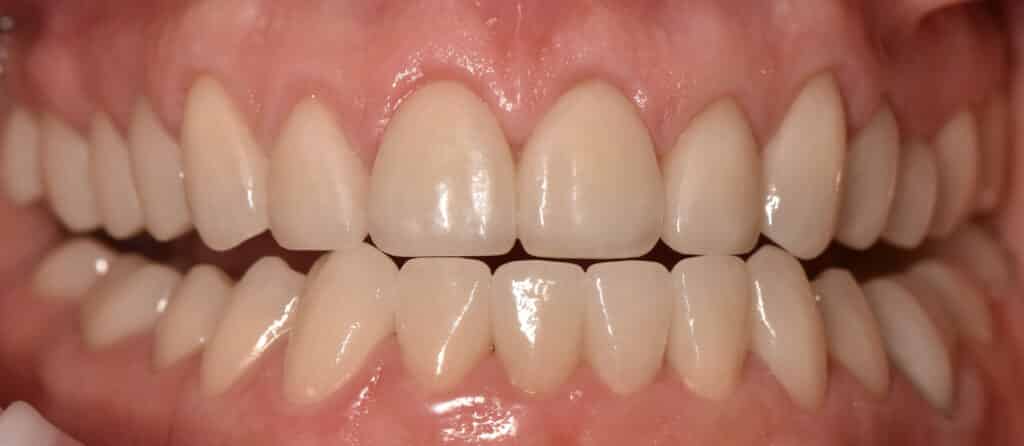

Die PMMA-Kronen wurden in der Zahnarztpraxis als Langzeitprovisorien für einen Zeitraum von drei Monaten eingesetzt (Abb. 16 bis 18). In dieser Zeit kann das Zahnfleisch verheilen und die Patientin hat Gelegenheit zu prüfen, ob sie mit der neuen Zahnkronenlänge gut zurechtkommt. Nach drei Monaten werden die Provisorien abgenommen, die klinische Situation mithilfe des IOS neu erfasst und auf dieser Basis die vollke-ramischen Restaurationen erstellt. Die Patienun Treut sich jetzt bereits aur das komplett neue Erscheinungsbild, ist aber auch aktuel schon senr zutrieden mit dem Ergebnis und glücklich, sich für die Behandlung entschieden zu haben.